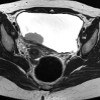

MRI of the bladder.

МРТ мочевого пузыря. Диагностический метод, позволяющий проводить неинвазивную оценку структуры и функции мочевого пузыря путем регистрации ядерного магнитного резонанса и формирования трехмерных изображений. МРТ мочевого пузыря дополняет результаты других инструментальных исследований (УЗИ, цистография, цистоскопия) и часто является решающим методом диагностики. Показаниями к МРТ мочевого пузыря могут быть патологическое развитие органа, опухоль, мочекаменная болезнь, инородные тела, нарушения мочеиспускания, оценка результатов хирургической или химиолучевой терапии. Процедура проводится на фоне наполненного мочевого пузыря, иногда в сочетании с МРТ почек.